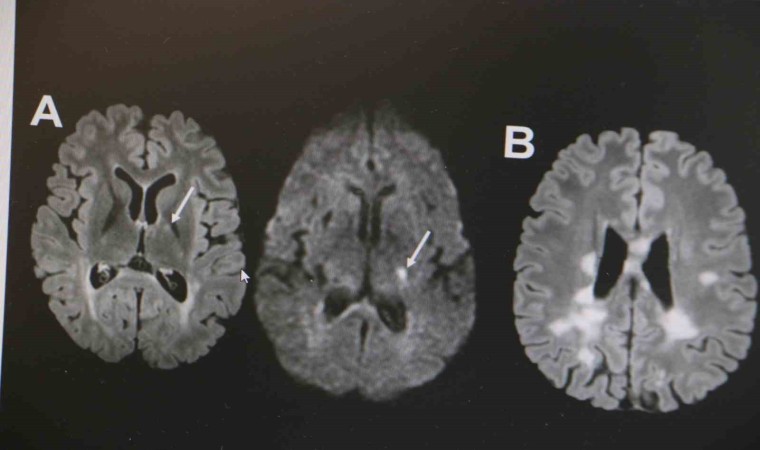

MS hastalığının kadın popülasyonunda daha sık görüldüğünün altını çizen Demir, "Kadınlarda erkeklere göre bu hastalık yaklaşık 2 kat daha sık görülmekte. MS hastalığı özellikle ataklarla seyreden bir hastalıktır. Hastaların yüzde 85’inde relapsing remitting form dediğimiz atak formuyla seyretmektedir. MS hastalığının tanısı klinik olarak kesin tanı konulabilse de günümüz şartlarında MR çekilmeden kesin tanı konulmaması önerilmektedir. MS hastalığının tedavisine gelecek olursak, kesin bir tedavisi yoktur. Ancak son 10 yılda çok sayıda ilaç kullanıma girmiştir. Bu açıdan MS hastalığı kontrol edilebilir bir hastalıktır. MS hastalığına bağlı ataklara karşı hastalara steroid tedavisi vermekteyiz. MS hastalarında görülen her şikayet atak olmayabilir. Özellikle idrar yolu enfeksiyonu, üst solunum yolu enfeksiyonu, aşırı egzersiz durumlarında, sıcak bir ortamda bulunma gibi durumda hastalarda ısı artışına bağlı olarak daha önceden var olan semptomlarda kötüleşme olabilir. Bunlar daha çok yalancı atak diyebiliriz. Ancak atak diyebilmemiz için şikayetin en az 24 saat sürmesi gerekmektedir" ifadelerinde bulundu.